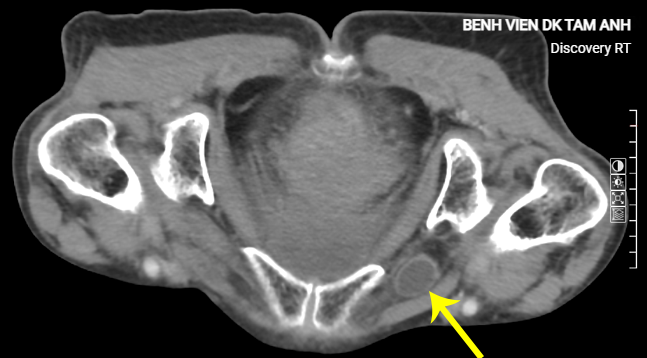

Bà có tiền sử viêm ruột, điều trị kháng sinh dài ngày không bớt, kết quả chụp CT tại Bệnh viện Đa khoa Tâm Anh cho thấy quai ruột non thoát vị bịt gây tắc ruột. ThS.BS Đào Văn Minh, khoa Ngoại tổng hợp, giải thích thoát vị bịt là tình trạng ruột chui qua ống bịt, một ống giải phẫu nằm sâu trong khung chậu, không thấy khối phồng, khó phát hiện, dễ chẩn đoán bỏ sót và chỉ chiếm dưới 1% số ca thoát vị.

Bệnh này thường gặp ở phụ nữ thể trạng gầy, như bà Thoa, cao 1,35 m, nặng 30 kg, chỉ số BMI 16,5 thuộc nhóm gầy độ hai. Do đường kính lỗ bịt ở phụ nữ lớn hơn nam giới, khung chậu rộng và nghiêng hơn khiến lỗ bịt càng mở rộng, tạo điều kiện cho thoát vị bịt.